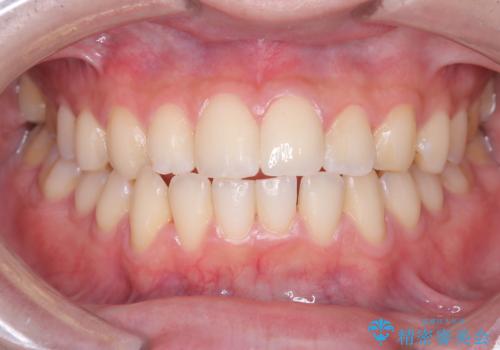

神経の状態が良好に保たれていることを確認した後、オールセラミッククラウンによる審美修復を行いました。

なお、最終補綴前にはオフィスホワイトニングを実施し、より自然で明るい仕上がりを得ることができました。

他院では「治療が難しい」と言われた患者様でしたが、当院で神経を残すことができ、見た目もきれいに仕上がったことで大変喜んでいただけました。